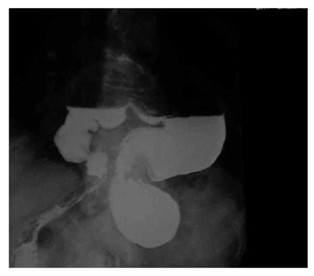

האבחנה נקבעת חד-משמעית על-ידי שיקוף דרכי העיכול העליונות, לאחר מתן חומר ניגוד. דרך זו נמצאה יעילה גם במקרים הכרוניים, אם כי לעתים די בצילום סקירה של בית החזה כדי להעיד על קיום פתלת הקיבה (תצלום 30.3).

| תצלום 30.3: פתלת הקיבה (צילום קיבה עם מילוי בריום – קיבה הפוכה) | |